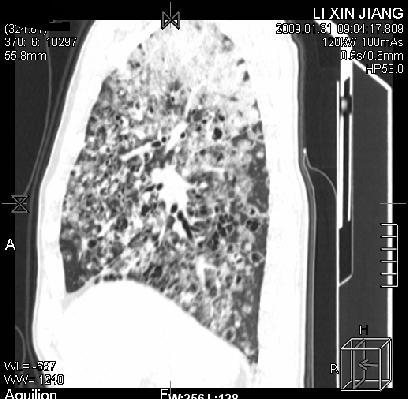

标题: CT18283:呼吸困难,明显喘息样呼吸 [打印本页]

呼吸困难,明显喘息样呼吸2个月

间质性肺病!还能用多久?

多为霉菌感染。

考虑两肺机遇性感染。

卡孢子虫肺炎(建议试验室查hiv,呼吸道分泌物找卡孢子虫)

机遇性感染,间质性病变

考虑:间质性病变伴两肺机遇性感染。

间质纤维化伴支扩。原因?

支持考虑:间质性病变伴两肺机遇性感染。

考虑 间质性病变伴两肺机遇性感染。